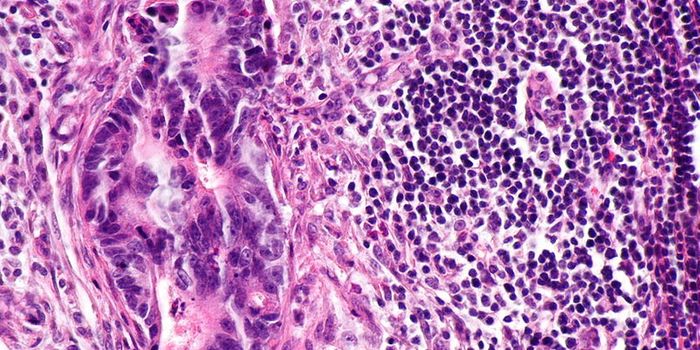

APR 11, 2022CancerOver 50 years ago, President Richard Nixon signed the National Cancer Act of 1971, a landmark piece of legislation ...